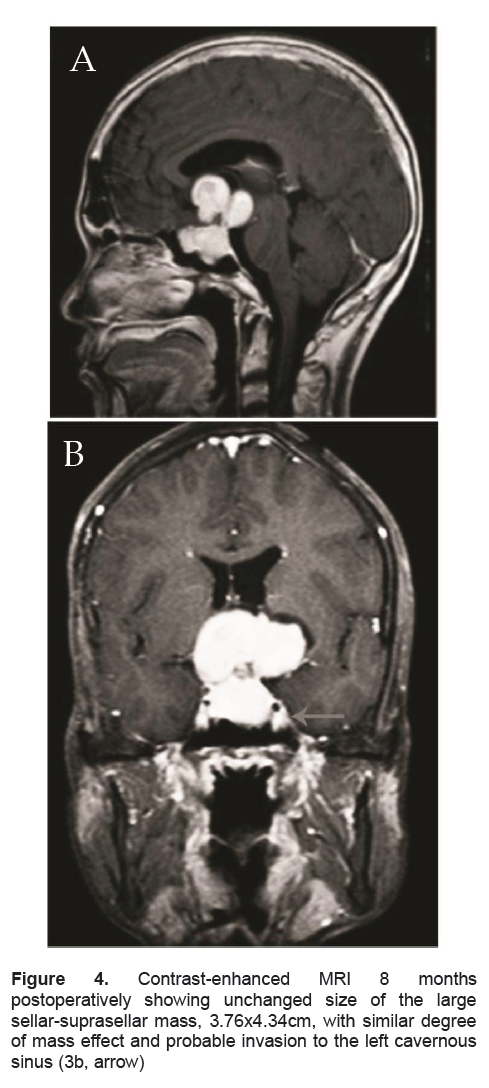

In the presence of elevated thyroid hormones, inappropriately high TSH and a pituitary macroadenoma with residual tumor after excision, a diagnosis of a TSH-producing Pituitary Adenoma was highly considered. Limited by the unavailability of alpha-subunit and TRH testing in our country, we only did immunohistochemical staining for TSH, which showed a negative staining (Figure 2b). Excision of the residual mass was advised. The patient and his family have agreed to another surgery but are financially constrained. His repeat FT4 and FT3 levels were elevated. His repeat MRI 8 months post-operatively revealed unchanged size of the sellar-suprasellar mass measuring 3.76 x 4.32 cm (Figure 4). Thyroid Scintigraphy revealed diffuse thyromegaly with high normal uptake (2-hr and 24-hr uptake at 11% and 41% respectively). The patient received methimazole, prednisone was continued and levetiracetam was discontinued, with no recurrence of seizure after discontinuation. Repeat thyroid function test 8 weeks after intake of methimazole showed improvement of his thyroid function tests. FT4 and FT3 were still elevated but lower than the previous test. TSH was inappropriately normal. At present, the patient remains clinically asymptomatic except for the visual field deficit.

Figure 4. Contrast-enhanced MRI 8 months postoperatively showing unchanged size of the large sellar-suprasellar mass, 3.76x4.34cm, with similar degree of mass effect and probable invasion to the left cavernous sinus (3b, arrow)